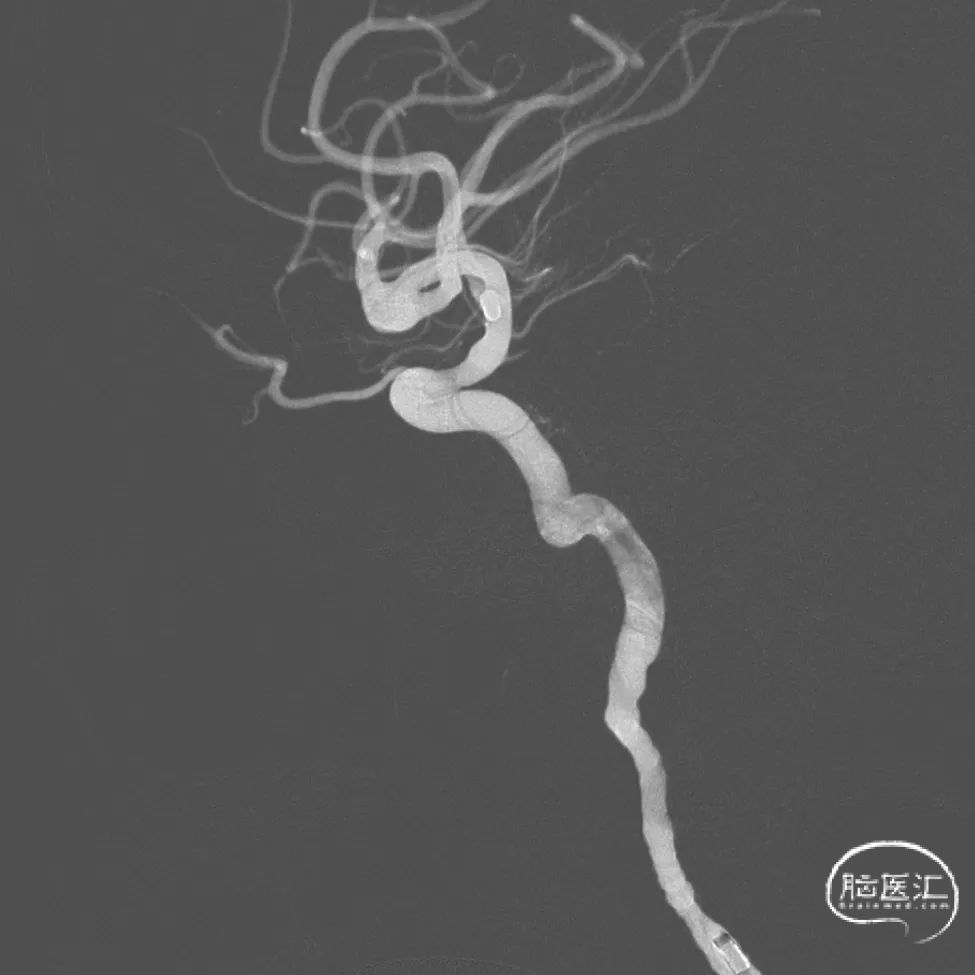

术前影像

术前MRA显示右侧MCA分叉部囊状动脉瘤,具体解剖细节不详。

术前DSA的正位、侧位造影。